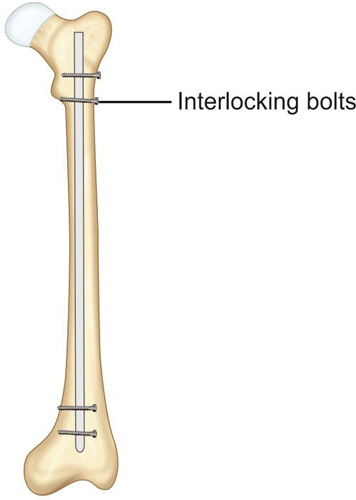

Intramedullary nail: First human intramedullary nail was done by Gerhard Küntscher in 1939.

It was a V-shaped steel nail which was later changed to hollow clover leaf model. This nail relied on a frictional fit between nail and bone. Since then intramedullary nailing has seen many changes in design as well as in technique. In 1942, Fischer introduced the use of intramedullary reamers to increase the contact area between the nail and host bone thus increasing the stability of fracture. Later Modney invented the interlock nails that get locked in bones to provide additional rotational stability in case of comminuted fractures (Fig. 1.44). Then in the 1960s, development of image intensifiers allowed surgeons to do intramedullary nailing with better confidence and with closed reduction (as explained in Fig. 1.40).

Principle of intramedullary nailing: Fracture is reduced under image intensifier and after reaming of medullary cavity nail is inserted into the medullary cavity which act as an internal splint to resist bending. Interlocking nails are provided with slots for locking bolts which prevent rotation and shortening.

Advantages of intramedullary nailing: It is ideal implant for long bone diaphyseal fractures. It can be implanted by minimally invasive technique without exposing the fracture hematoma. Thus it is a biological method of fracture fixation.